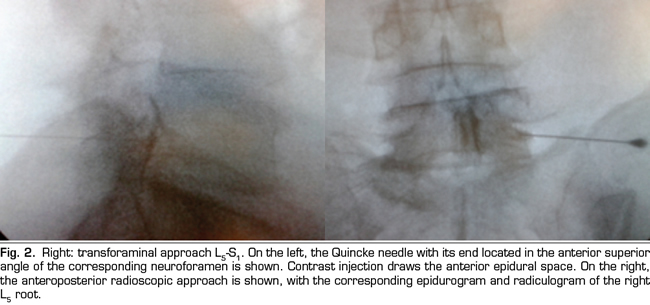

Results: Fifty four patients were treated with epidural betamethasone. In 29 the parasagittal interlaminar route was utilized while 25 were treated by the transforaminal route. A 20 % reduction in baseline VNS was observed with the interlaminar route and 36 % reduction with transforaminal approach. Intensity and Interference Scores were also reduced. This reductions were statistically significant when comparing to baseline data (paired t test) but differences between groups were not significant (unpaired t test). However the number of positive responses as defined above was greater in the transforaminal group, 64 % versus 38 % in the interlaminar group, statistically signifi cant difference using the Chi Square analysis (p=0.01). In patients with positive responses, interlaminar and transforaminal betamethasone produce clinical and statistically significant reductions in pain intensity and interference, without difference between groups.

Conclusion: Epidural betamethasone produced a reduction in pain intensity and interference utilizing the BPI, by the two routes utilized to access the epidural space. Although no statistically differences were observed in this reductions between groups, the frequency of positive responses were higher when the drug is administered by the transforaminal route. Epidural interlaminar parasagittal betamethasone injection is a reasonable alternative to the transforaminal route, without the neurologic complications described utilizing this technique.